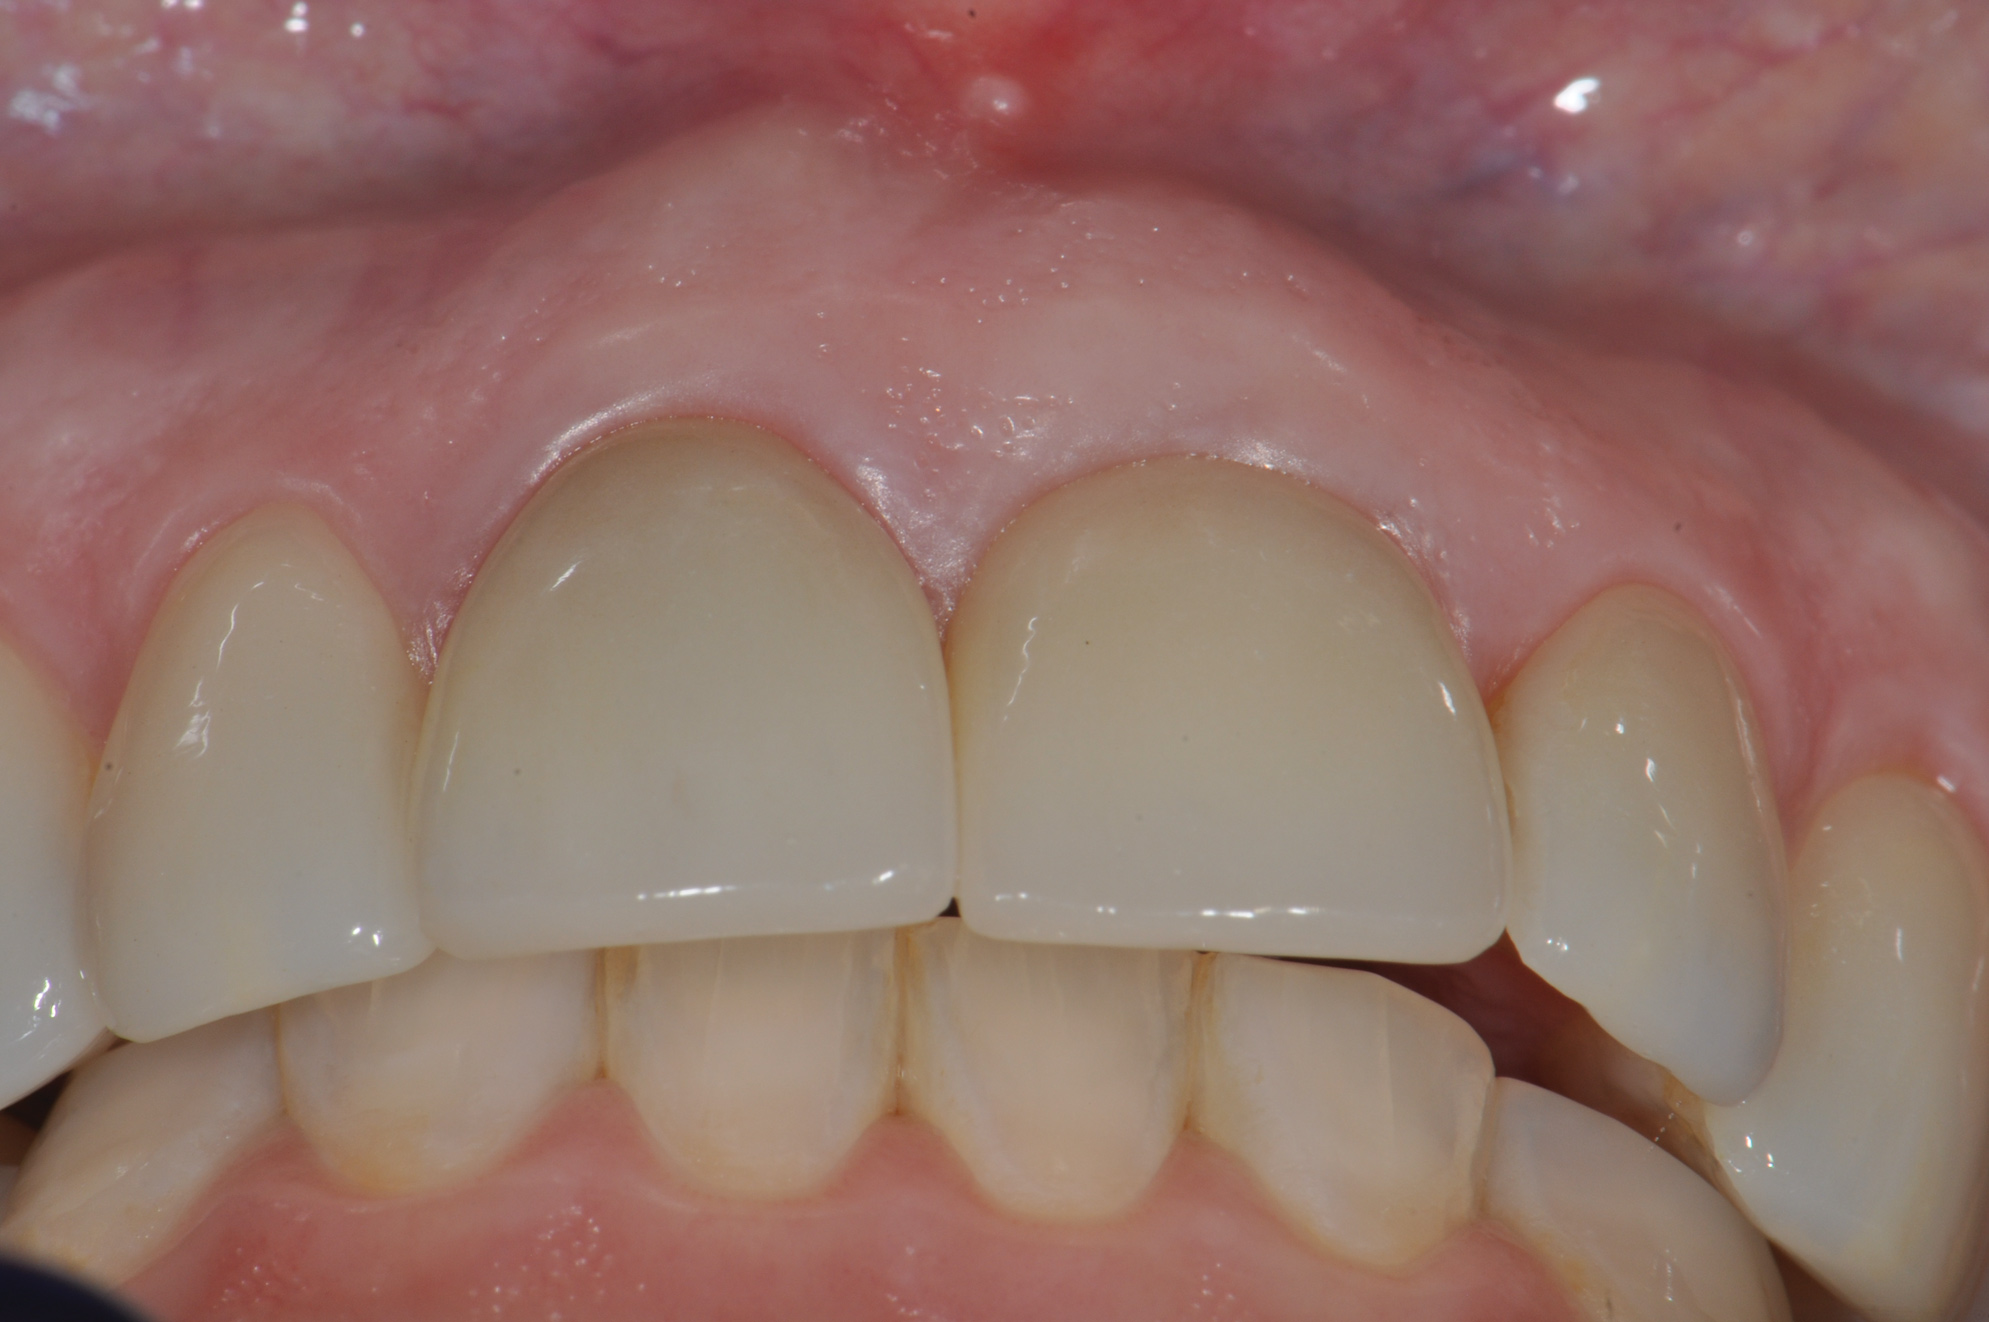

Finally, another example of an "unlucky" esthetic outcomeis illustrated in Figure 17 through Figure 19, which show the 3-year postoperative follow-up of the fully guided (coDiagnostix®, Dental Wings, dentalwings.com) 3D placement of No. 7 and No. 10 implants (Straumann Bone Level Narrow Connection Roxolid® SLActive, Straumann) in a 34-year-old high esthetic risk profile female patient with non-loading of both implant sites. For this patient, eight of the 10 keys were followed, with the exceptions being key Nos. 7 (SCTG) and 8 (immediate contour management). Esthetic complication was noted, especially on implant No. 7, with a facial bony concavity with loss of ridge width and show-through of the titanium custom abutments (ie, "graying" of soft tissues) due to colorimetric changes of the marginal tissues.

Fig 17. Facial (Fig 17) and occlusal (Fig 18) views, 3 years postoperative, of implants Nos. 7 and 10, fully guided with 3D placement of 3.3-mm x 12-mm implants with non-loading of both sites. Patient was high esthetic risk profile. Key Nos. 7 (SCTG) and 8 (immediate contour management) were not used. Facial bony concavity with loss of ridge width was noted on No. 7 along with show-through of titanium abutments (periodontist: Jeff Ganeles, DMD).

Figure 17

Fig 18. Facial (Fig 17) and occlusal (Fig 18) views, 3 years postoperative, of implants Nos. 7 and 10, fully guided with 3D placement of 3.3-mm x 12-mm implants with non-loading of both sites. Patient was high esthetic risk profile. Key Nos. 7 (SCTG) and 8 (immediate contour management) were not used. Facial bony concavity with loss of ridge width was noted on No. 7 along with show-through of titanium abutments (periodontist: Jeff Ganeles, DMD).

Figure 18